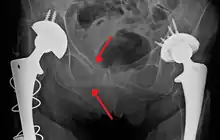

Surgery

Surgery is often required for pelvic fractures. Many methods of pelvic stabilization are used including external fixation or internal fixation and traction.[18][19] There are often other injuries associated with a pelvic fracture so the type of surgery involved must be thoroughly planned.[20]